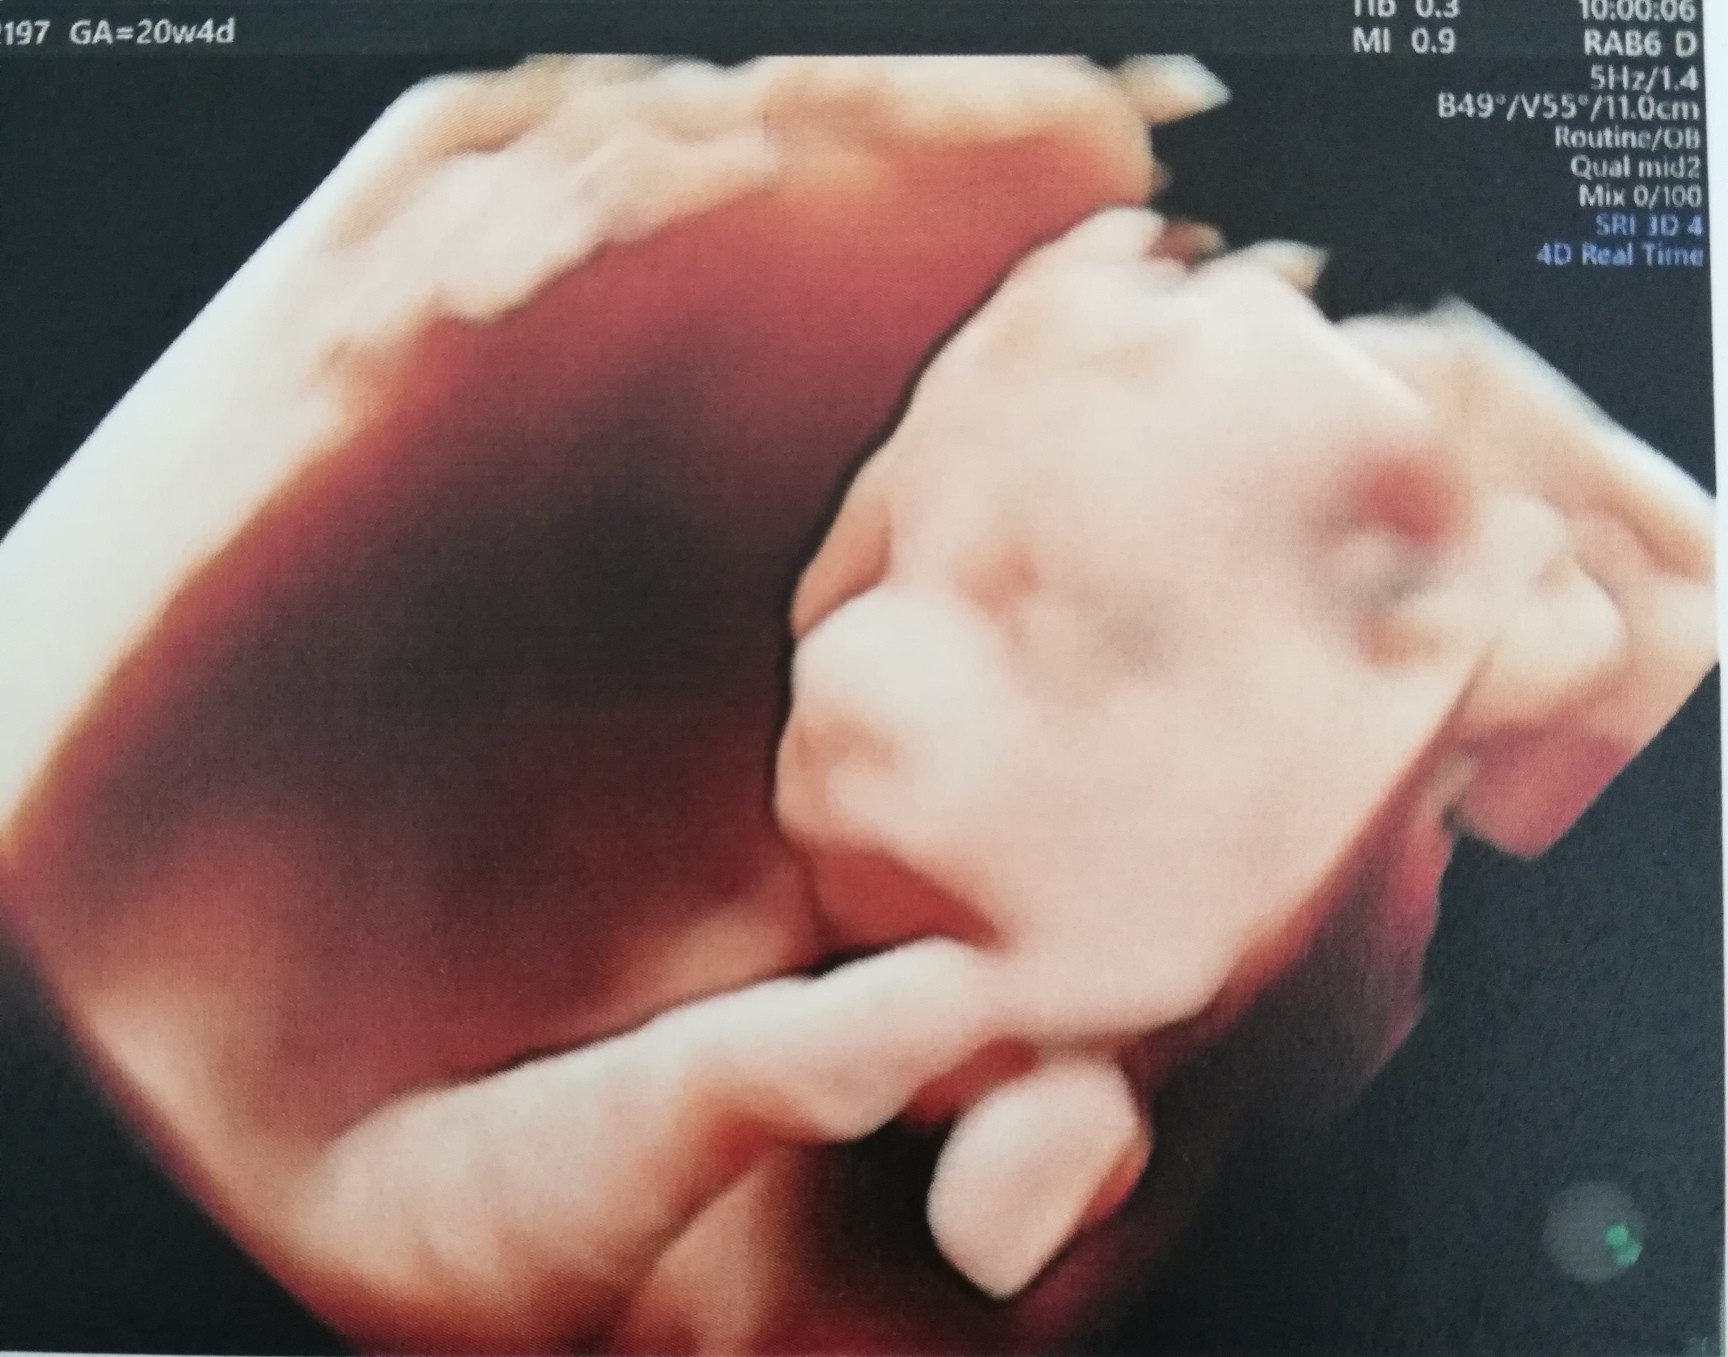

My nareszcie po badaniach prenatalnych :D

Józef zdrowy jak ryba i długaśny, czyli marne szanse na urodzenie dziecka mniej jak 3500g.

Wyszedł miarami poza siatki centylowe.

503g i 15,5 cm :D dwa tygodnie do przodu.